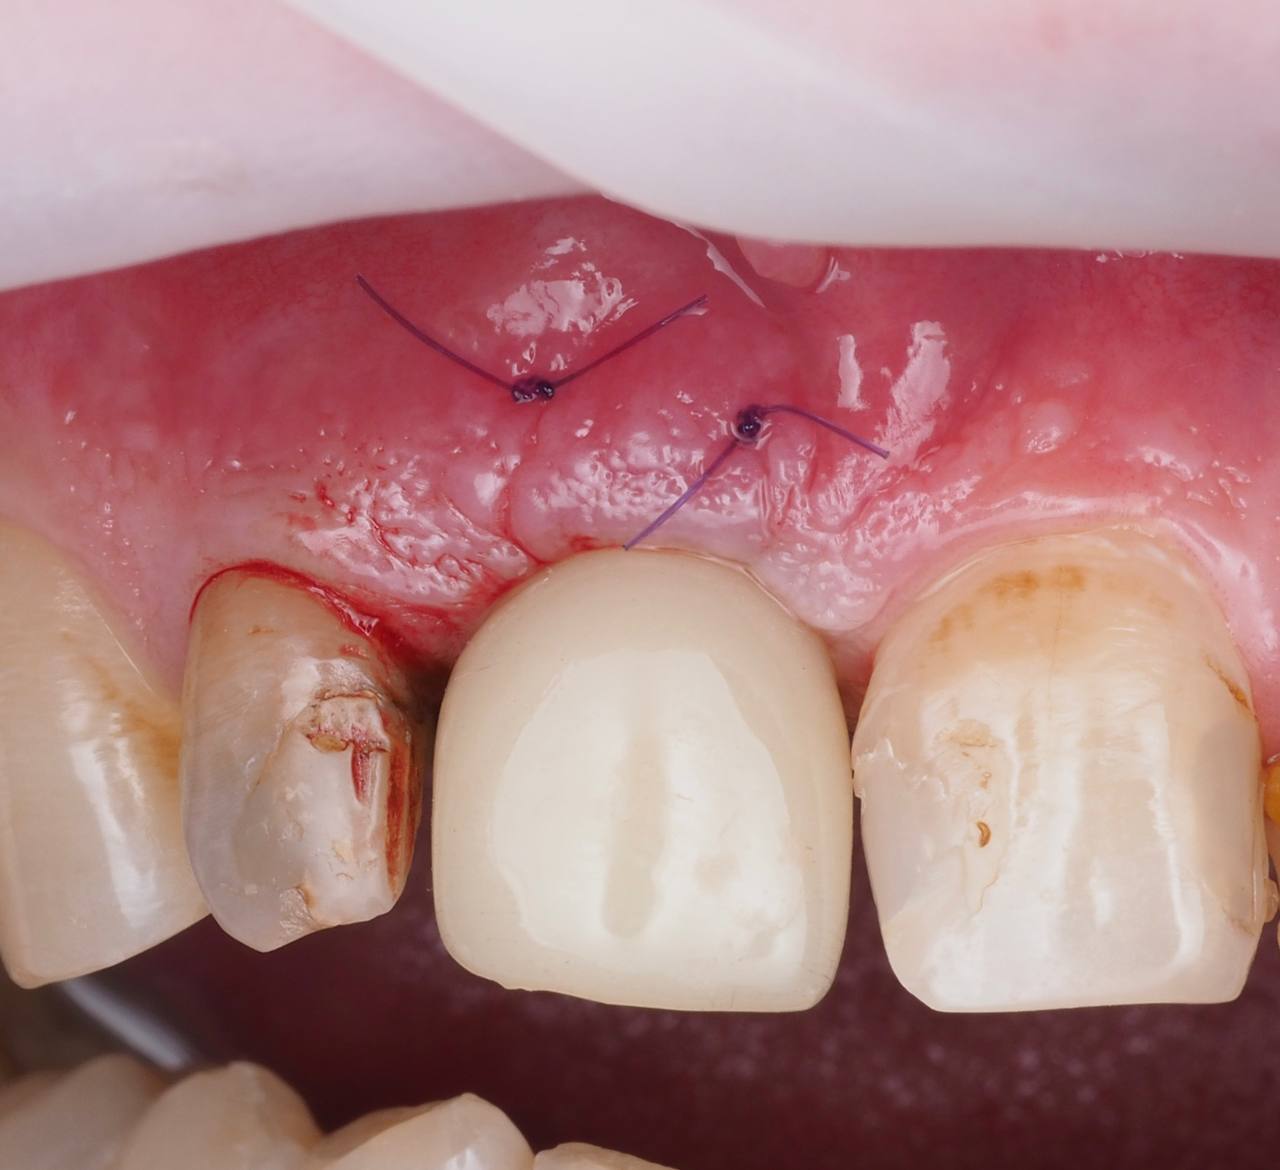

Одномоментная имплантация 1.1

AnyRidge, мультиюнит Octa, CCT, временная коронка